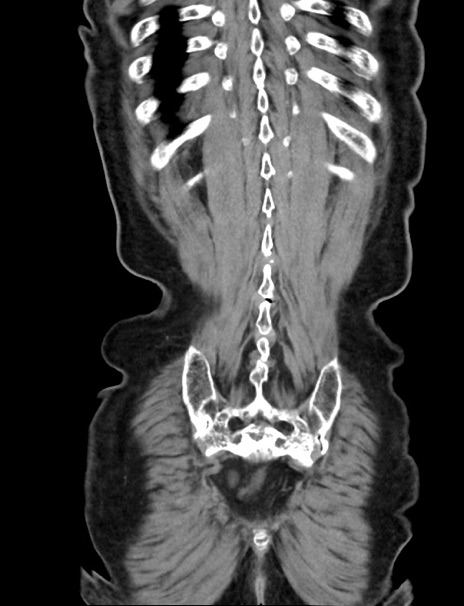

症例33(冠状断像)

【症例】70歳代 女性

【主訴】心窩部痛

【現病歴】延髄病変の精査・加療にて神経内科入院中。本日より心窩部痛あり。

【身体所見】右下腹部を中心に圧痛と反跳痛あり。

【データ】WBC 10900、CRP 0.02